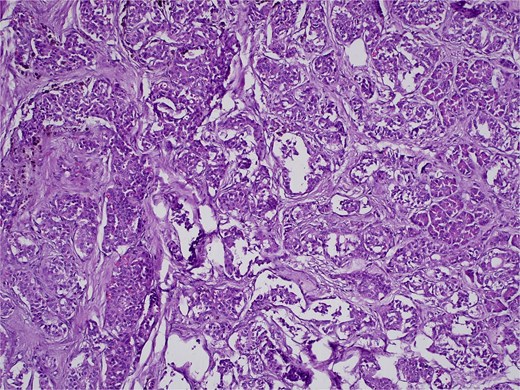

On 27 January 2025, the patient underwent a Whipple procedure (pancreaticoduodenectomy). The surgery included cephalic pancreatectomy with reconstruction through hepaticojejunostomy and gastrojejunostomy in a Roux-en-Y configuration. Gross pathology revealed a firm, white-yellow, indurated mass in the pancreatic head measuring 3.7 × 3.5 × 3 cm with irregular borders and central hardness (Fig. 4). Histopathological analysis confirmed a Grade 1 neuroendocrine tumor (insulinoma), with a Ki-67 index of 2%. The tumor showed direct extension to adjacent pancreatic tissue, the duodenal muscularis propria, the adventitia, and the muscularis of the common bile duct. Five peripancreatic lymph nodes were dissected, three of which were positive for metastases (Figs 5–9).

H&E stain, 100× magnification. Irregular clusters of neoplastic cells with vascular invasion.